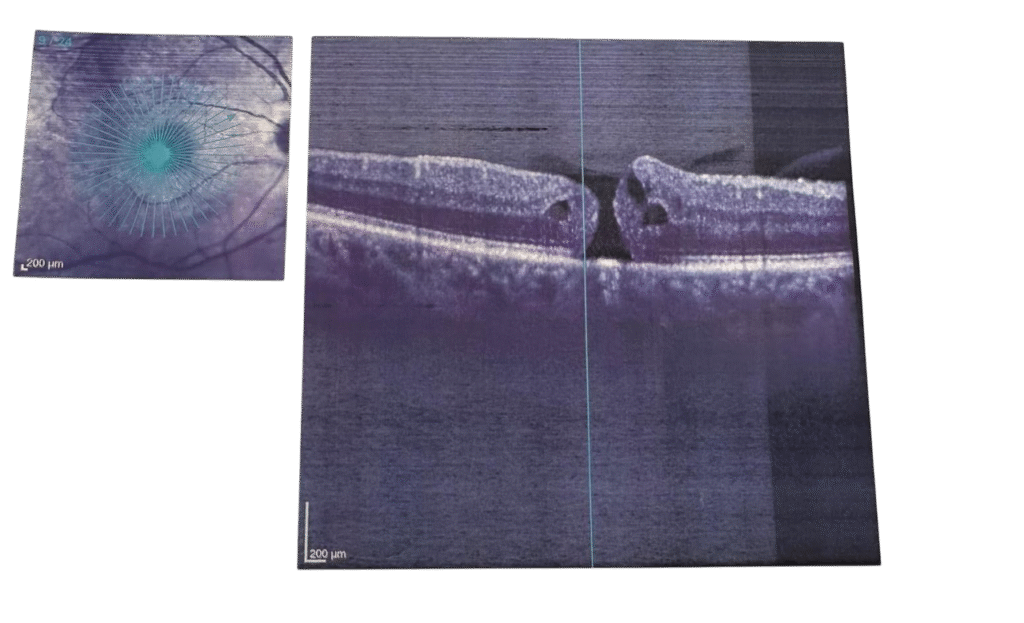

Resim 1: Makula deliği öncesi

Tanı

Gözün ‘MR’ ı veya ‘TOMOGRAFİSİ’ olarak da düşünülebilecek bu işlem , saniyeler içinde makula tabakalarının mikron düzeyinde kesinti alınır. Deliği çapı, evresi ve yapısı OCT ile net bir şekilde belirlenir

Evreleri

Evre 3 : Orta boy delik vitreus ayrılmıştır

Evre 4 :Delik + Tam vitreus ayrılması